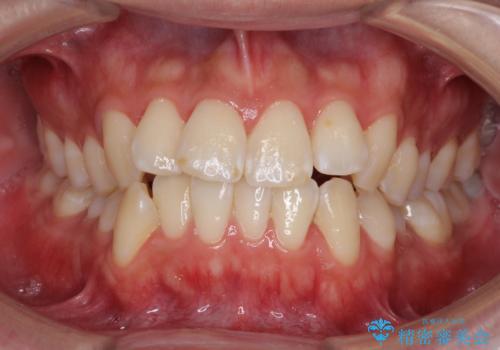

[インビザライン ライト] 短期間(3.5ヶ月)で終わるマウスピース矯正

![[インビザライン ライト] 短期間(3.5ヶ月)で終わるマウスピース矯正の症例 治療前](https://seimitsushinbi.jp/wp/wp-content/uploads/2020/02/C3-500x350.jpg?v=1580813654)